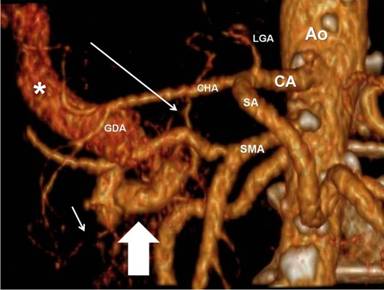

A 75-year-old female performed a quadriphasic abdominal CT examination for the characterization of a focal hepatic lesion, previously identified with a transabdominal ultrasound. Patient had a chronic HCV infection. The physical examination was substantially negative: particularly, the patient did not show any sign or symptom related to the pancreatic arteriovenous malformation or to gastrointestinal bleeding. The MDCT showed a hypervascular area of 3.5x2.5 cm in the pancreatic head, constituted of ectasic vessels (Figure 1); no calcifications were seen inside the mass. The lesion did not determine mass effect or dilation of the main pancreatic duct. During the arterial phase, there was also an early filling of the portal vein and the proximal portion of the superior mesenteric vein. Para-coronal maximum intensity projection and 3D electronic reconstructions made possible to identify the arterial afferents to the malformation (Figure 2), constituted by small aberrant branches from left gastric artery (Figure 3) and posterior inferior pancreaticoduodenal artery (Figure 4); it was also possible to identify the venous efferent drainage, constitute by the portal vein (Figure 5) and the superior mesenteric vein (Figure 6). Other MDCT findings were: presence of a cirrhotic liver with a solid 3.0x2.5 cm mass in the II segment, hyperdense in the arterial phase with washout during the portal phase, referable to hepatocellular carcinoma; an aberrant replacing right hepatic artery arising from the superior mesenteric artery; and a 1.5 cm solid hypodense lesion in the pancreatic body, with fat density and without contrast enhancement, referable to pancreatic lypomatosis.

Figure 2. 3D paracoronal maximum intensity projection arterial phase reconstruction, showing the pancreatic arteriovenous malformation (solid arrow) and their arterial afferents arising from the left gastric artery (long arrow) and the inferior posterior pancreaticoduodenal artery (short arrow). Note the improper portal venous flow toward the liver (asterisk). Ao: aorta; CA: celiac artery; CHA: common hepatic artery; GDA: gastroduodenal artery; LGA: left gastric artery; SA: splenic artery; SMA: superior mesenteric artery |